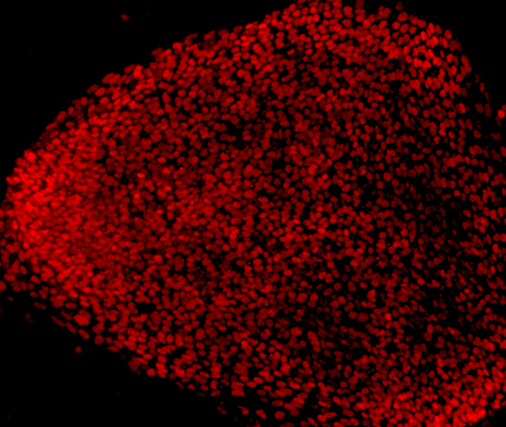

Japanese researchers recently announced that a red food coloring has been found to be effective in the treatment of malignant glioma through animal experiments. It is expected that new therapeutic drugs will be developed on this basis...